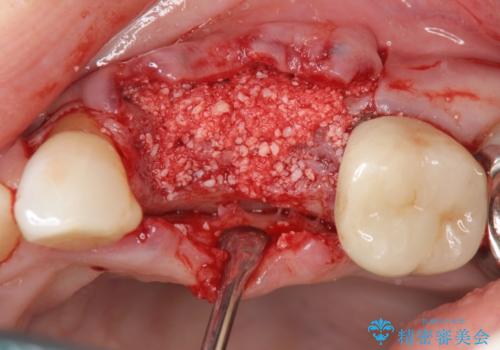

抜去後の補綴治療は長いブリッジではなくインプラント治療を希望されましたが、穿孔・破折による周囲の骨吸収をリカバリーすべく骨の造成を伴うインプラント治療を計画します。

インプラント治療を行うにはインプラント周囲に十分な骨の幅・高さが必要です。

今回はが原因で失われてしまった骨の幅を回復することで長期的な予後を見込めるインプラント治療を行うことができました。